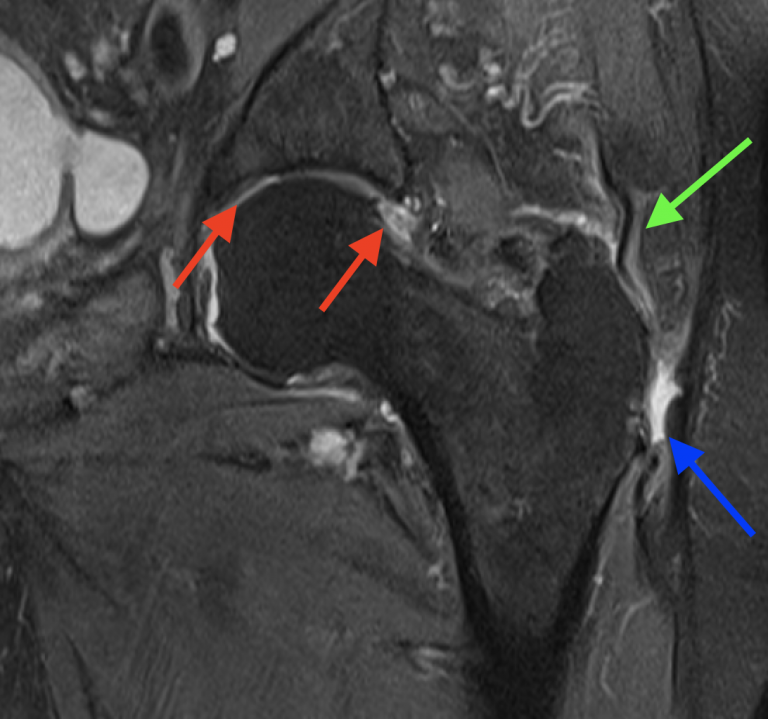

(A) Isolated partialthickness gluteus medius tear. T2weighted coronal What Is A Partial Thickness Tear Of Gluteus Medius Tendon The most typical symptom is pain down the side of your hip and through the buttocks. Learn about the anatomy, diagnosis, and treatment options, including exercise, prp injections, and surgery. Common symptoms of gluteal tears. This review article summarizes the anatomy, clinical presentation, and treatment options for gluteus medius and minimus tears,. Tears in the gluteus medius and minimus tendons,. What Is A Partial Thickness Tear Of Gluteus Medius Tendon.